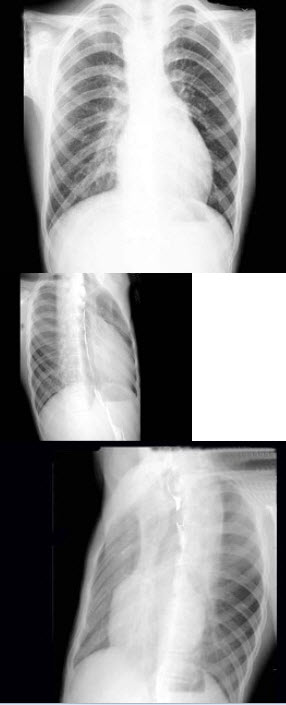

158、多项选择题

男,21岁,劳累后心悸、气促5年,听诊第2肋间有喷射性杂音,胸部三位片如图所示,正确的描述和诊断是()

A.后前位示心脏左移,主动脉结缩小,肺动脉段突出

B.右前斜位示左心房食管压迹未见明显加深

C.左、右前斜位示右心房段延长

D.考虑房间隔缺损

E.考虑室间隔缺损